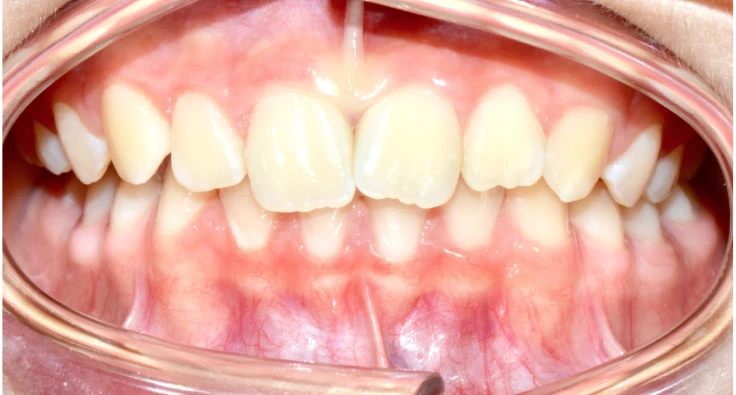

Objectif de l’occlusion De face

- Milieux centrés (flèches noires)

- Secteurs latéraux emboités (cercles jaunes)

Objectif de l’occlusion De profil

- Occlusion molaire de Classe I (flèches vertes)

- Occlusion canine de Classe I (flèches bleues)

- Guide antérieur (Cercle rouge)